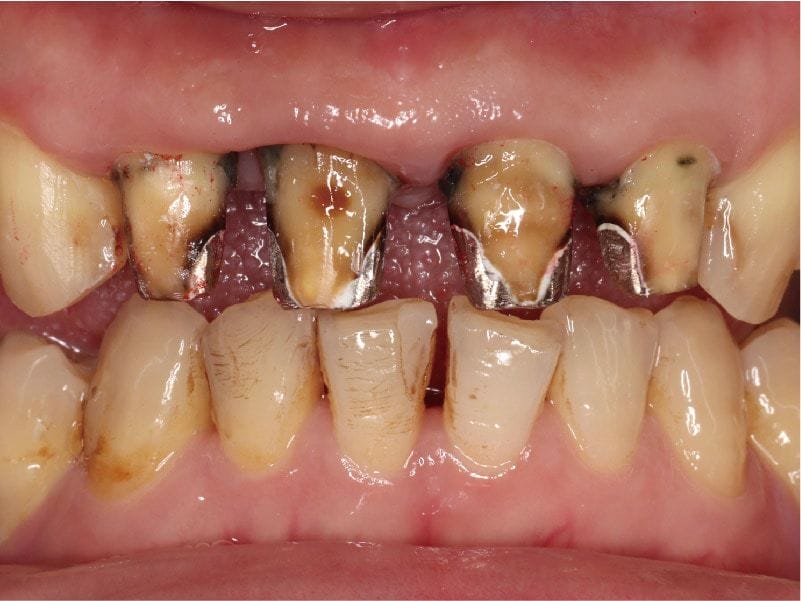

圖示:Mr.Lin左下臼齒牙齦近照與X光片,可看到大範圍填補痕跡和牙隨、牙周問題

針對牙周病,從環口式X光片初步檢測出齒槽骨流失的狀況,並配合部分牙齒牙周囊袋的檢測,我們可以由此診斷出Mr.Lin也有全口牙周病需要治療。

他舊有的門牙假牙,剛製作時並沒有縫隙,而是後來才越來越明顯而影響外觀。其實這在牙周病或是缺牙患者很常見,問題根源在於,因嚴重牙周病會導致牙齒沒有辦法負擔咬合力量,或是臼齒缺牙後未重建而習慣用前牙咀嚼。

若是前牙本身牙周支撐力量不足,甚至還承擔臼齒缺牙的咬合力量時,這樣會使前牙發生咬合傷害(occlusal trauma),產生病理性位移(pathologic migration)現象,這導致門牙產生間隙,並且越來越突出,形成暴牙影響外觀。其實很多人並不清楚這是牙周病的症狀與後遺症之一。

圖示:舊門牙假牙位移產生縫隙,且突出形成暴牙,是典型的牙周病症狀與後遺症